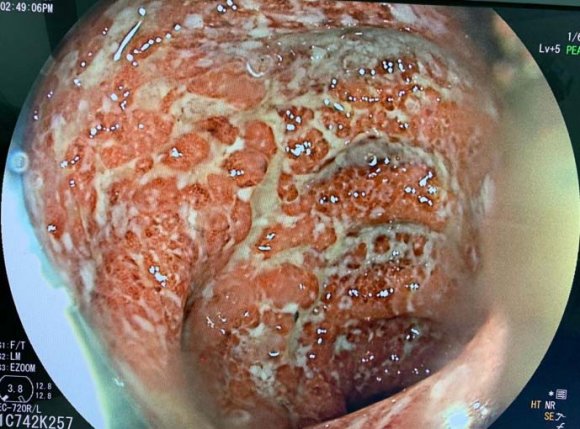

The patient was admitted again 6 months later, she developed bloody diarrhea with abdominal pain, and tenesumus, colonoscopy revealed inflamed hyperemic colonic mucosa with multiple active ulcers, Hemoglobin (Hb) was 9.1 g/dl (normocytic), white blood cell count was 12.44 × 103/ml (neutrophilic leukocytes: 90.8%, lymphocytes: 7.4%), and platelets were 3 × 105 /?l, C-reactive protein(CRP) and erythrocyte sedimentation rate were 78 mg/dl and 35 mm/h respectively. The patient was therefore treated with intravenous corticosteroids (1mg/kg/day) for 7 days then with PSL 50 mg/day, and azathioprine was switched to 6 mercaptopurine (6MP) 75mg/day, this was followed by clinical and biological improvement.

A year and two months later, the patient was admitted for an UC attack, she was having Bloody diarrhea as well as severe tenesmus and rectal bleeding, colonoscopy revealed inflamedfriable mucosa severely hemorrhagic. Bblood test reveled anemia with Hb: 8.4 g/dl (normocytic), white blood cell count was 15.333 x 10 3 /ml, CRP was 120 mg/dl, stool studies were negative for infection. Intravenous corticosteroids as well as corticosteroid and 5-ASA enemas were begun and the patient showed clinical and biological improvement (number of bloody diarrhea diminished as well as CRP (40 vs 120). The colitis was then considered an immunomodulator refractory colitis, and we had to consider another treatment to maintain remission.